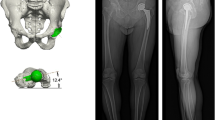

The low-dose bi-planar radiographs (EOS imaging, Paris, France) have been developed as a new method for clinical implant position analysis, which allows patients to be evaluated in standing posture [9, 10]. With two perpendicular X-ray beams mounted on a vertically traveling C-arm, the system scans all or part of the body and produces projections in two perpendicular planes simultaneously. Additionally, the system employs dedicated software (sterEOS, EOS imaging, Paris, France) to adjust generic models of the hip and femur, thereby, generating highly accurate 3D models of the patient’s bone and THA prosthesis, which can be used for assessing prosthetic orientation parameters in standing position, including cup anteversion, cup inclination, and stem anteversion [11]. The low-dose bi-planar radiographs can, thus, provide two sets of parameters: one with the anterior pelvic plane (APP) as the reference plane, which is defined by both anterior superior iliac spines (ASIS) and the pubic symphysis (Fig. 1A) [12], while the other with the radiographic coronal plane (functional coronal plane). Some previous studies have already evaluated the accuracy of measurements of femoral, tibial, and femorotibial torsion using the low-dose bi-planar radiographs [13,14,15,16,17]. Demzik et al. [18] analyzed inter-rater and intra-rater repeatability, and the reliability of pelvic parameters.

A-D The reconstruction process is a software-guided step-by-step procedure. A Identifying the sacral plate, the sacroiliac joints, the acetabula, the pubis and the anterosuperior iliac spines. B Adjustment of the 3D ellipse on the border of the acetabular cup. C Identifying the key landmarks on the femur, the position of the trochlear notch and condyles, and adjustment of the prosthetic head. D Adjustment for the position of the prosthetic neck’s landmarks and identifying the inferior extremity of the stem

EOS measurements

The EOS biplanar radiographs were obtained with the patients in a weight-bearing standing position. The reconstruction process was a software-guided step-by-step procedure, including identifying anatomical landmarks (Fig. 1). Recognition of anatomical landmarks is crucial for accurate measurements. At the same time, we obtained the parameters with the functional coronal plane as the reference plane. The cup anteversion was anatomical, and the inclination was radiographic [24]. The femoral stem neck axis was defined as the axis passing through the center of the femoral head and the mid-point of the stem neck. The posterior condylar axis was defined as the axis passing through the most posterior points of the medial and lateral condyles. Stem anteversion was defined as the angle between the neck axis and the posterior condylar axis projected in the plane orthogonal to the femoral mechanical axis (Fig. 2). PT was defined in the sagittal plane between the line connecting the midpoint of the sacral plate and the midpoint of the acetabular axis, and the vertical axis.

A-D The pelvis and femur are 3D reconstructed. A Identification of the acetabular axis by the edge of the cup. B Identification of the sacral crest. C Identification of the bilateral anterior superior iliac spine (ASIS) and pubic tubercles, and the midline of bilateral ASIS. D Definition of the stem anteversion as the angle formed by the axis of the femoral neck and the posterior tangential line of femoral condyles